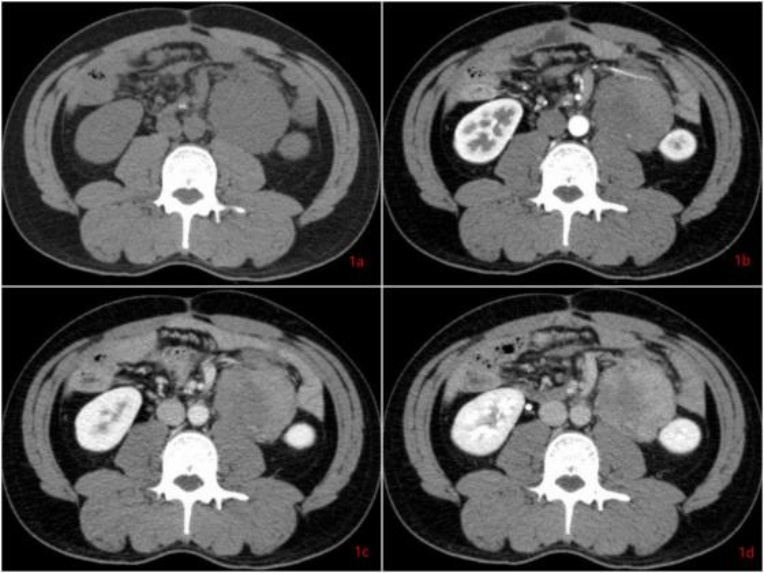

患者男,41岁。1年前气管插管全麻下行腹腔镜全大肠切除术,术后病理提示:家族性腺瘤样息肉病伴乙状结肠中分化管状腺癌。术后行“奥沙利铂 + 卡培他滨”化疗6次,化疗期间肿瘤指标正常。1年后复查全腹CT所见:左肾前下方及肠系膜内亦见多发肿块,较大者位于左肾前下方,大小约2.7 cm × 2.3 cm × 3.6 cm (左右径 × 前后径 × 上下径),边界光整,等密度;动脉期轻度强化,内见血管穿行;静脉期及延迟期呈渐进、延迟不均质强化,内见低密度区,肿块与左侧输尿管上段分界不清,以上肾盂积液轻度扩张,再经3个月后,复查全腹CT (图1图2)提示腹腔肿块明显增大,病灶大小约6.6 cm × 5.7 cm × 8.7 cm (左右径 × 前后径 × 上下径)。随后完善腹部MR (图3),所见:左肾前下方见及肠系膜内亦见多发长T1不均匀长T2信号影,弥散未见明显受限,增强扫描呈渐进性不均匀强化,内见无强化坏死区,肿块局部向后压迫左侧输尿管上段并分界不清,以上输尿管及肾盂轻度积液扩张。综合CT及MR影像诊断:转移瘤可能性大。但患者体重稳定增加,复查肿瘤指标仍未见异常,影像诊断与临床不符。

Figure 1. Plain CT and dynamic contrast-enhanced CT imaging in the long-axis plane

1. CT平扫及动态增强长轴位

计算机断层扫描(Computed Tomography, CT):CT平扫通常表现为边界不清或境界较清的软组织密度肿块,密度多为等或稍低于肌肉密度,内部可见条索状或斑片状低密度区(代表黏液变性或坏死,相对少见)。增强扫描动脉期轻度强化,静脉期及延迟期呈进行性不均匀强化,这与肿瘤富含纤维组织、对比剂缓慢渗透有关。对于腹腔内病变,CT可清晰显示肿瘤与肠管、血管的关系,评估有无肠梗阻、肾积水等并发症。但CT对软组织分辨率有限,对肿瘤内部结构细节的显示不如MRI。